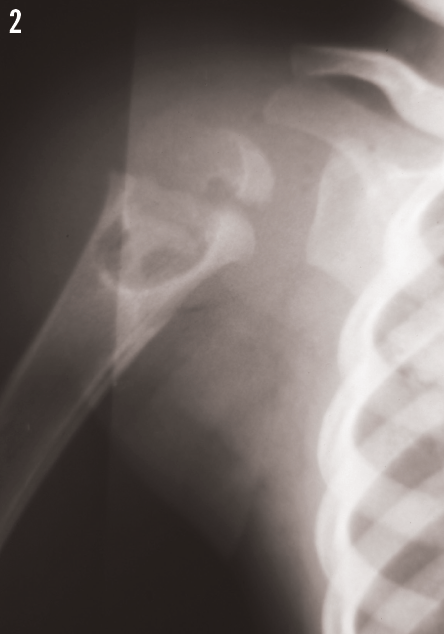

Radiographs of the right shoulder demonstrated a large cystic lesion in the proximal humerus with a lytic process extending across the physis into the epiphysis proximally. A large paratracheal lymph node also was noted on radiographs of both the chest (Figure 1) and the shoulder (Figure 2).

How do you interpret these images?